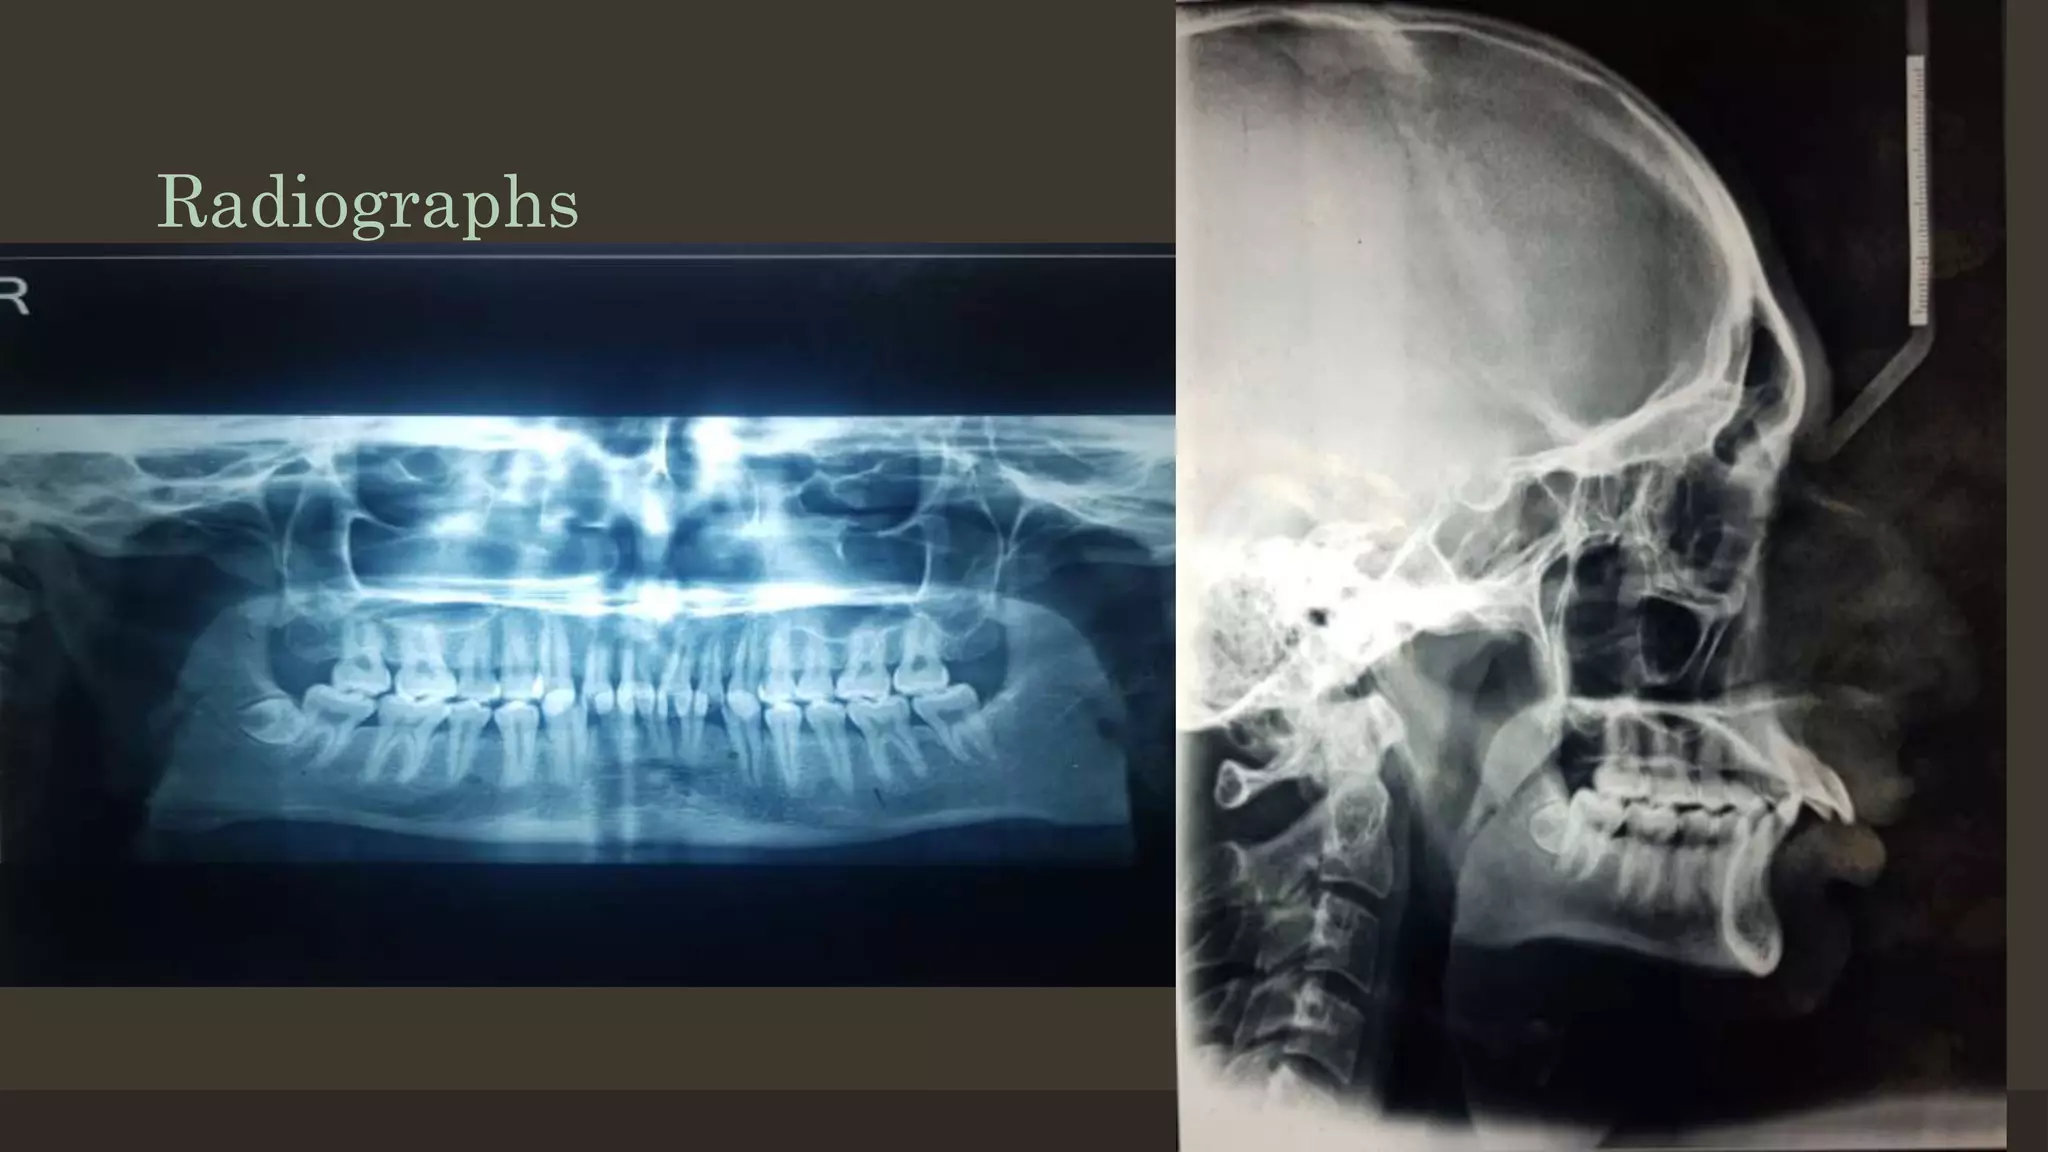

Radiographs

12/19/2020 83